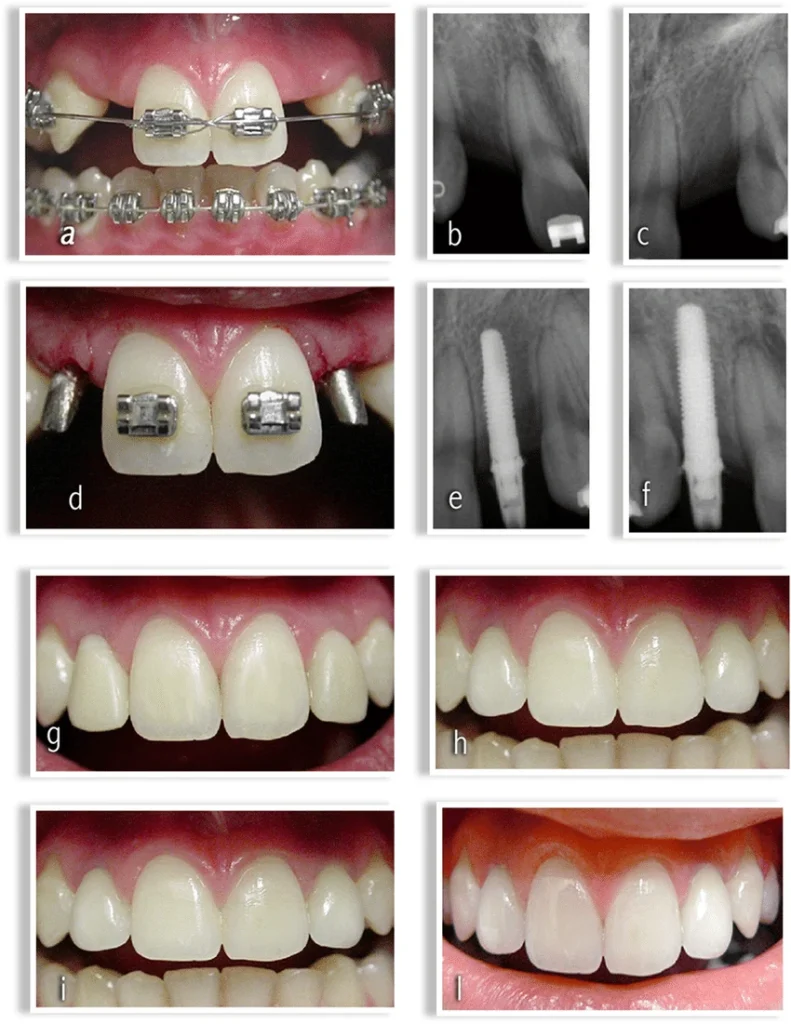

Le traitement des agénésies bilatérales des incisives latérales supérieures repose sur deux grandes options thérapeutiques, chacune présentant des variantes. Une concertation étroite entre l’orthodontiste et le dentiste prothésiste est essentielle pour déterminer la meilleure approche en fonction des caractéristiques cliniques du patient.

Option 1 : Conservation ou Augmentation des Diastèmes pour les Incisives Latérales

- Implants dentaires : Une option à long terme, souvent envisagée en fin de croissance.

Option 2 : Déplacement des Canines en Position d’Incisive Latérale avec Fermeture des Diastèmes Antérieurs

Traitement Orthodontique

Conservation ou Augmentation des Espaces

- Traitement précoce : Vise à établir des relations de classe I molaires nettes, souvent à l’aide d’un fil élastique buccal (FEB) sur bagues.

- Traitement tardif : Repositionnement des canines en classe I et fermeture des diastèmes inter-incisifs à l’aide d’un dispositif multi-attaches.

- Coronoplastie : Réalisée avant le traitement orthodontique pour ajuster la forme des dents.

- Dispositif multi-attaches : Indispensable pour un alignement précis.

- Finition esthétique : Reconstitution des angles des dents à l’aide de composites chargés.

- Rééquilibration occlusale : Meulage de la cuspide palatine de la première prémolaire supérieure (en position de canine) ou utilisation d’un onlay palatin.

Approche Multidisciplinaire

Une collaboration étroite entre l’orthodontiste, le prothésiste, et parfois le parodontiste est nécessaire pour évaluer les conditions initiales et planifier le traitement. Les décisions doivent intégrer les attentes du patient, les contraintes socio-économiques, et les limites biologiques (par exemple, la hauteur de gencive ou l’épaisseur de la corticale osseuse).